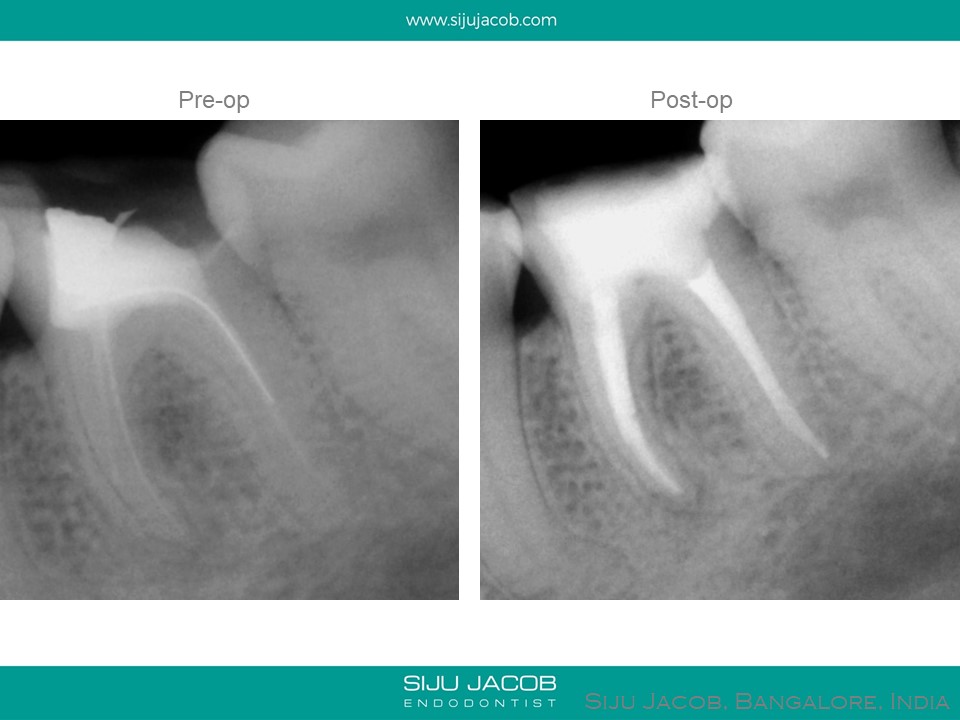

This is a case from 2006. Sometimes, when you look at these cases, we realize how much our treatment philosophies have changed over the years. This tooth was asymptomatic and the endo done several years ago. So, what benefit did me doing the re-endo have? Other than being a better “process centered outcome”, from a patient centered outcome, did it really matter? In fact, I probably made the prognosis worse by removing too much tooth structure. These days, when we get a case like this, we have a discussion with the patient before treating. Sometimes, we leave cases like these alone (No re-endo) and advise just a permanent restoration.